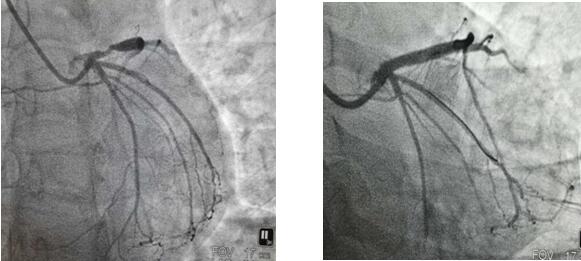

4月22日上午,患者王女士因“反复胸痛、胸闷半年”就诊我院,行冠脉造影提示LAD段严重狭窄,经全面评估患者病情,充分结合患者及家属意愿后,今日上午为31岁的王女士成功植入生物可吸收支架一枚,手术过程顺利,术后效果满意。

支架植入前                         支架植入后